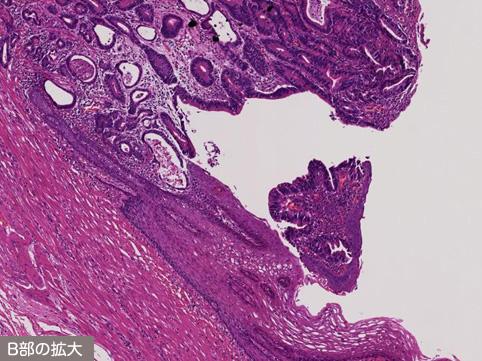

疾患(病理主体)の分類悪性上皮性腫瘍/腺癌

部位(臓器別)2つ以上の臓器/

検査方法ミクロ

腫瘍の肉眼分類0型(表在型)/IIc型(IIc+IIa)

病変の最大径(ミリ)25〜29

腫瘍の深達度sm